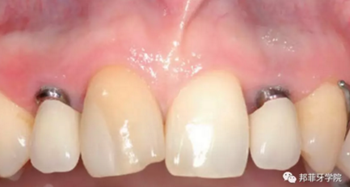

牙齦成型器周圍應(yīng)嚴(yán)密縫合,防止唾液進入切口(圖9)。X線片顯示植體位置理想(圖10)。愈合期未見并發(fā)癥,植體周圍牙齦愈合良好(圖11)。十周后取模,椅旁制備臨時牙(圖12),并制作螺絲固位PEEK基臺。

圖 11:植入10周后口內(nèi)情況

圖 12:椅旁制備臨時冠

最終印模采用個性化印模柱,記錄穿齦輪廓(圖13)。CAD/CAM個性化基臺精確就位(圖14)。全瓷冠水門汀固位(圖15)。